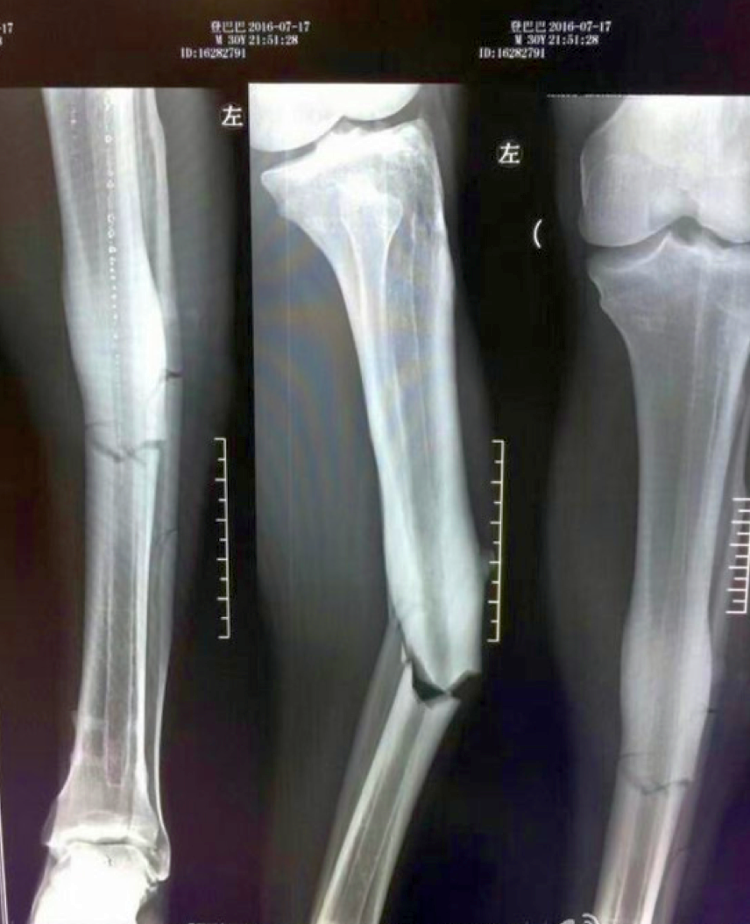

In functie de specificul accidentului tibia se poate fractura atat de a lungul osului diafizei cat si in partile extreme fractura de maleola fractura platoului tibial. Buna seara am vut acum 3 ani la varsta de 36 de ani o ruptura deschisa de tibie si peroneu. Specialistul avertizează că tratamentul lor ridică probleme uneori destul de dificile. între genunchi și gleznă și articulat la cele două capete cu tibia formînd fluierul piciorului sau gamba.

Buna ziua acum 10 zile mi am fracturat tibia si peroneul cu deplasare la 5 cm deasupra gleznei de atunci am gips. De când erau doar două celule osoase ce sugeau calciu lactic cu biberonul înfipt în cavităţi dar care se credeau deja măduvă. Tibia este osul cel mai mare și mai puternic dintre oasele gambei celălalt fiind fibula tibia conectează femurul cu oasele piciorului este găsită lângă fibulă în partea mediană și anterioară a gambei. Fibula fibula sau peroneul este un os lung subțire pereche pe partea laterală a gambei ce pare torsionat pe axul său situat lateral și posterior față de tibie cu care se articulează la cele două extremități ca orișice os lung el prezintă un corp și două extremități proximală și distală.

Tibia şi peroneul voiau sa crească împreună ca oase pereche unite n epifize. Tibia şi peroneul sunt cele două oase ce alcătuiesc scheletul gambei spune medicul sebastian diaconescu. Nici in ziua de astazi nu sunt recuperat flexare gleznei este destul de proasta cu pocnituri si feseori cu dureri. A purtat 15 luuni o tija metalica de 20 cm cu suruburi dupa care la rugamintea mea a fost extrasa.

In extremitatea inferioara tibia se articuleaza cu astragalul si peroneul componente ale articulatiei gleznei. Peroneul se articuleaza in extremitatea superioara cu tibia formand platoul tibial iar in cea inferioara maleola externa cu tibia si astragalul.